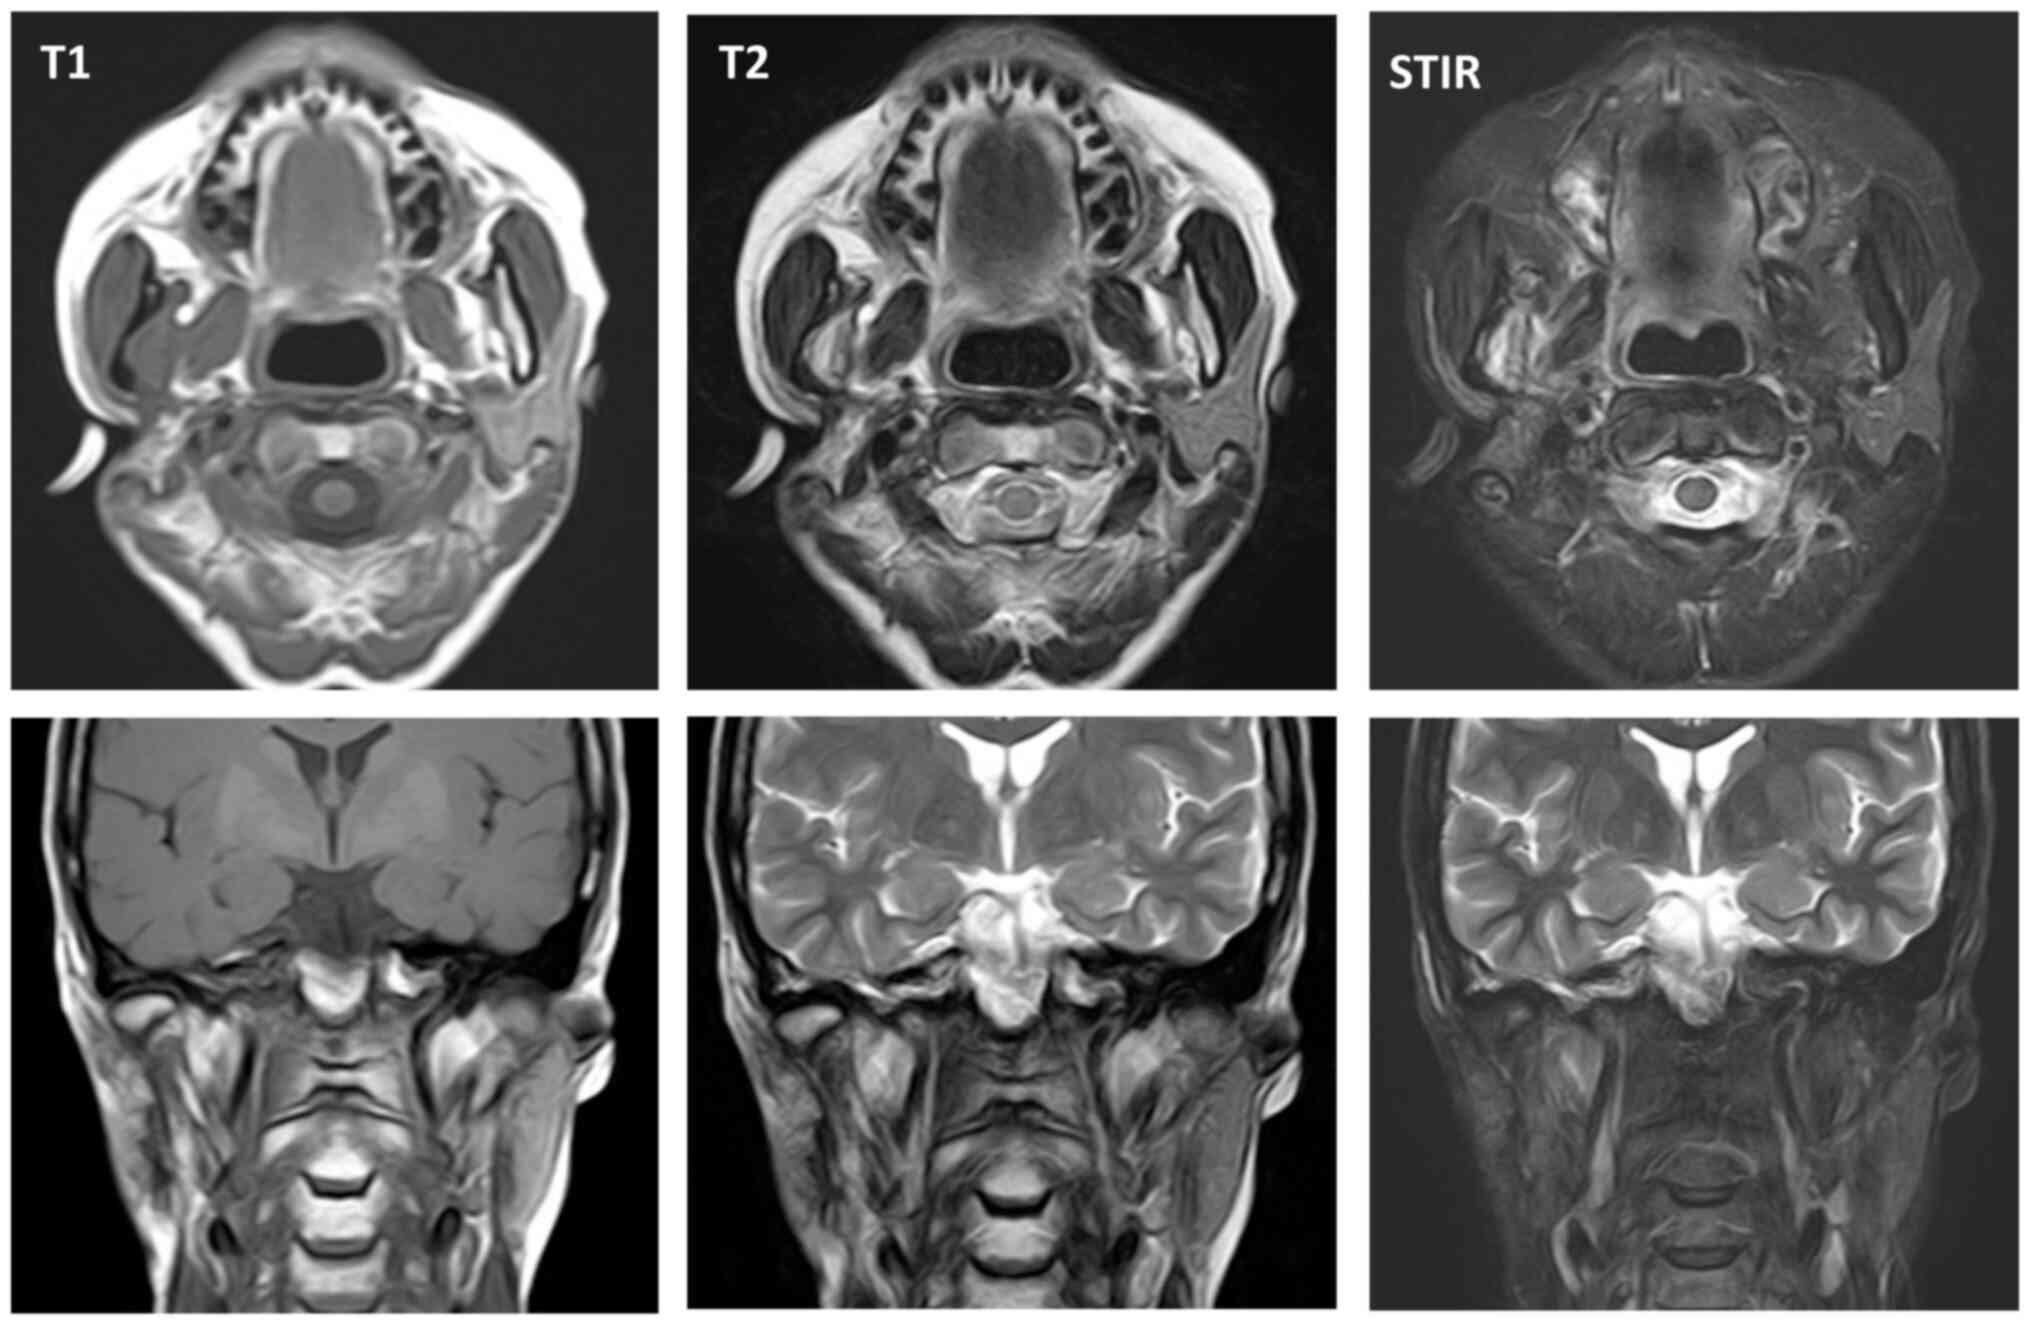

At five months post referral the lower part of the right auricula displayed swelling. Computed tomography (CT) and magnetic resonance imaging (MRI) revealed a space occupying mass (52×50×40 mm) in the infratemporal fossa (Figs. 2 and 3). Fine needle aspiration biopsy (FNAB) was performed at this site and hemoid gelatinous fluid was withdrawn. However, pathological examination of the sample did not lead to final diagnosis. Parotid gland tumor, neurilemoma, primitive neuroectodermal tumor (PNET), conventional HPC, and SFT were cited as differential diagnoses.

Figure 3.

Magnetic resonance imaging (MRI) before treatment.